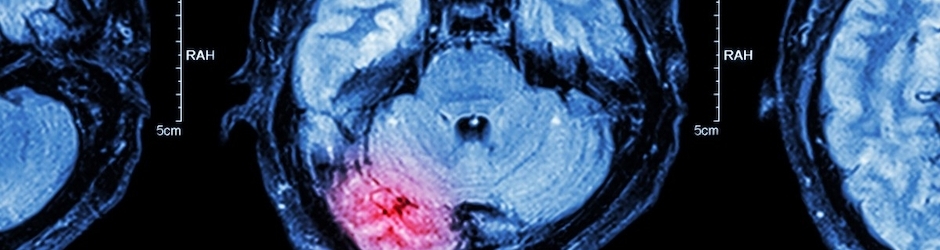

Cerebellar Ataxia